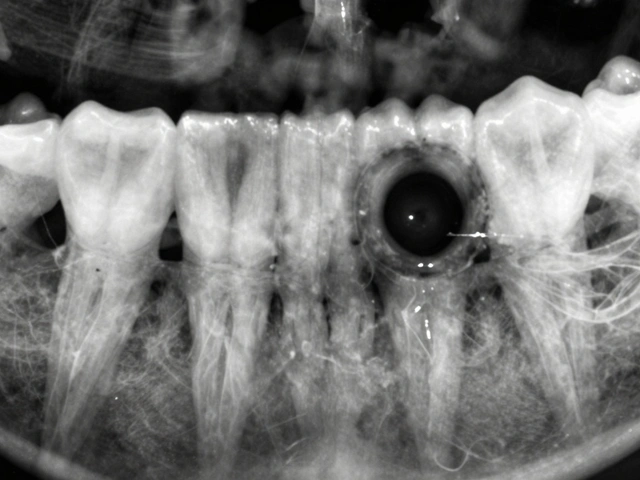

První krok k řešení problému praskliny na zubu je její správná identifikace. Praskliny se mohou projevovat různě - od téměř neviditelných po velmi zřetelné. Některé z běžných příznaků zahrnují pocit bolesti při žvýkání, zvýšenou citlivost na teplé nebo studené pokrmy a nápoje, a v některých případech i viditelné trhliny na povrchu zubu. Vzácněji může člověk pocítit bolest při otevírání úst nebo při stisku zubů.

Je důležité si uvědomit, že ne všechny praskliny jsou okamžitě viditelné. Někdy se nachází pod gumou nebo jsou příliš jemné na to, aby bylo možné je vidět pouhým okem. Proto pokud máte podezření na prasklinu na zubu kvůli výskytu výše uvedených příznaků, doporučuje se co nejdříve navštívit zubaře. Praskliny nejenže způsobují bolest a nepohodlí, ale také mohou vést k dalším zdravotním problémům, jako jsou infekce nebo dokonce ztráta zubu.